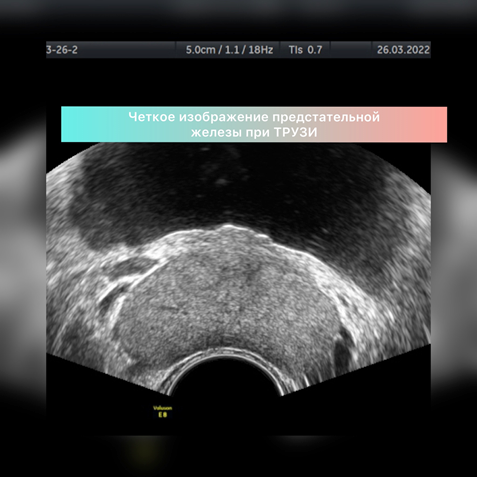

УЗИ предстательной железы возможно проводить двумя методами: датчиком через переднюю брюшную стенку (трансабдоминально) и датчиком через прямую кишку (трансректально) - ТРУЗИ.

В результате УЗИ-осмотра через прямую кишку информации гораздо больше. Возможна визуализация зон предстательной железы, подробное изучение простатического отдела уретры, состояние семенных пузырьков, визуализация мелких кист или участков фиброза, очаговых образований малых размеров.

• Для трансректального осмотра особой подготовки не требуется. В идеале – акт дефекации в день исследования. Исследование проводится лежа на левом боку с подтянутыми к животу коленями. Датчик покрывается одноразовой латексной насадкой – презервативом для УЗИ, на который наносится специальный водорастворимый гель, который облегчает введение датчика в прямую кишку. Толщина датчика около 2 см. он вводится на глубину 3-4 см. Исследование в большинстве случаев длится 1-2 минуты. Изображение с монитора выводится на экран телевизора, доступного для пациента. При этом врач может наглядно объяснить, какие есть изменения.